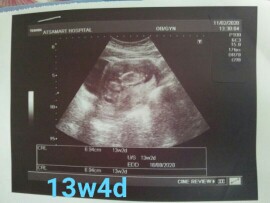

บ้านนี้13w4dจ้า